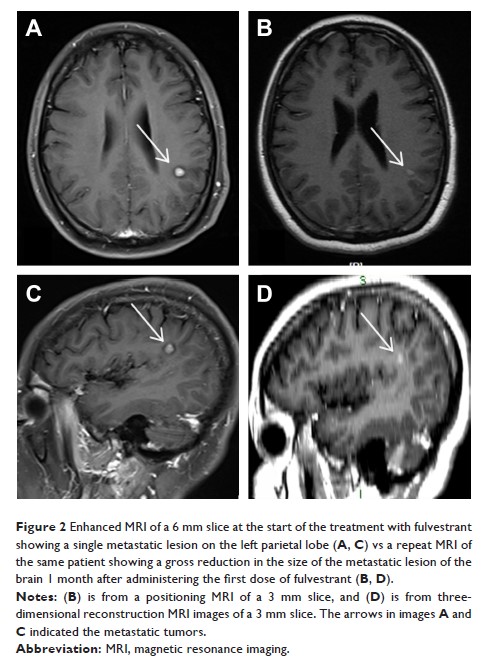

Case Series

- 作者:Qian Wang, Bing Sun, Chao Liu, Sanzhong Shi, Lijuan Ding, Jiannan Liu, Shikai Wu

- 期刊:OncoTargets and Therapy